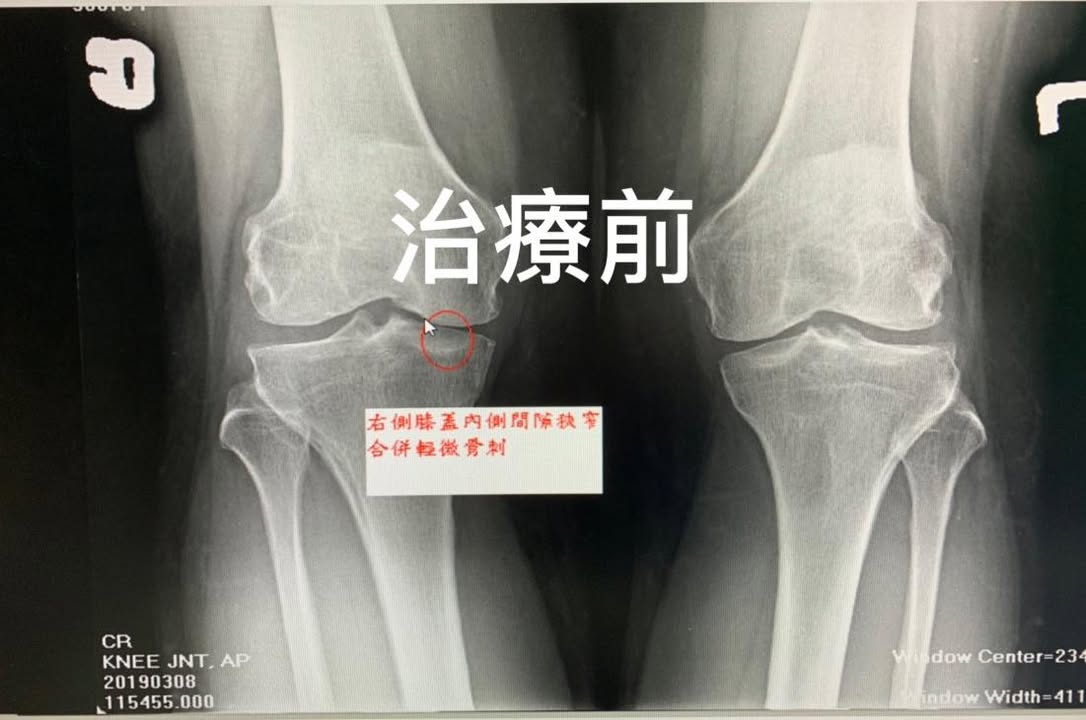

Cervical Spine Treatment Cases 膝關節案例 #退化性膝關節炎醫案 #膝關節整合針刀醫學療法 #有圖有真相前後對比照片 #內側皺襞針... 2020.10.16 #感謝中和呂小姐熱情見證 #膝關節疼痛超過十年 #看遍名醫打過五次PRP仍然沒效 #髕下脂... 2020.03.19 #退化性膝關節炎醫案 #膝關節整合針刀醫學療法 #有圖有真相前後對比照片 2019.09.07 #膝關節退化性關節炎醫案分享 #疼痛半年以上打過三次玻尿酸還痛 👉膝關節微創內側皺襞... 2019.08.15 #退化性膝關節炎醫案 #膝關節整合針刀醫學療法 #有圖有真相前後對比照片 #內側皺襞針... 2019.06.26 #膝關節疼痛兩年打了三次PRP效果不如預期怎麼辦 ▶️膝關節超微針刀整合治療如何處理 ☑️... 2019.03.17 #退化性膝關節針刀整合療法 #前後X光對比間隙打開 #針刀醫學療法讓您看到希望 2019.02.27 #退化性膝關節炎一定要開刀嗎 #除了玻尿酸或是PRP還有其他選擇嗎 #膝關節內側皺襞針刀... 2019.03.01 #退化性膝關節針刀整合療法 #前後X光對比間隙打開 #針刀醫學療法讓您看到希望 #看到患... 2019.02.16 #退化性膝關節炎第三期醫案 #治療前後影像對比 #針刀醫學療法真的做到打開膝關節間隙... 2019.02.01 #膝關節疼痛數年醫案 #謝謝八十多歲徐伯伯跟徐阿姨熱情見證針刀醫學療法 2018.12.26 1